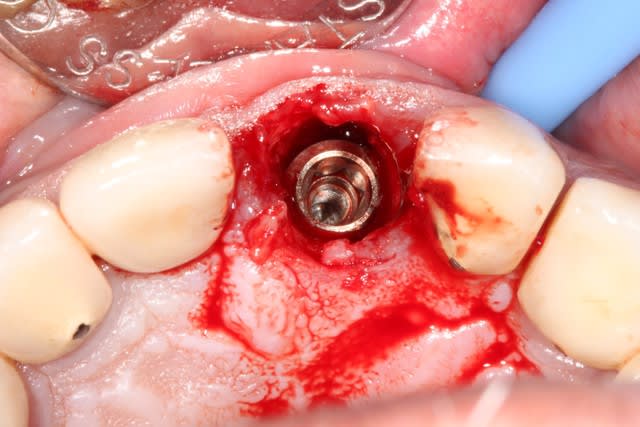

2/ extraction + forage lingualé

3/ pose d'un implant Dentium SuperLine 5/14 en ménageant un espace avec l'os vestibulaire

4/ comblement avec de l'osteon de l'espace vestibulaire, mais aussi d'un autre espace

cet espace est une poche sous périostée qui est créé en vestibulaire de l'os vestibulaire, il faut évidemment ne pas déchirer le périoste.